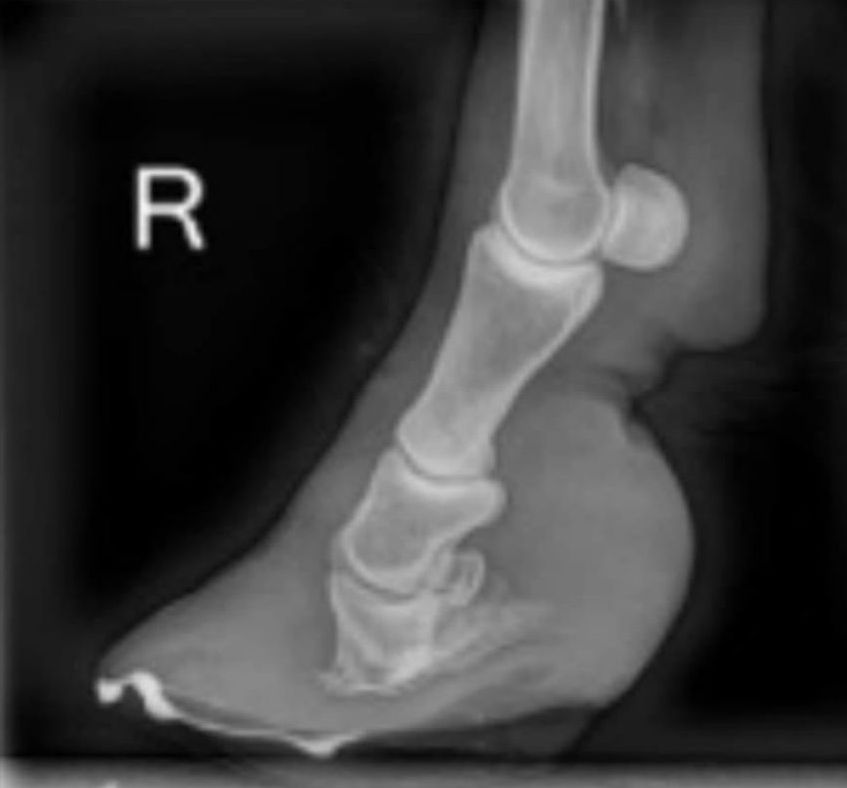

Der Tierarzt wird dein Pferd mit Medikamenten versorgen und am besten ein Röntgen machen.

Das Röntgenbild ist wichtig damit man sieht ob und wie sich das Hufbein in seiner Lage verändert hat. Die Hufpflegerin kann mit dem Bild ein Optimales Rehepolster machen.